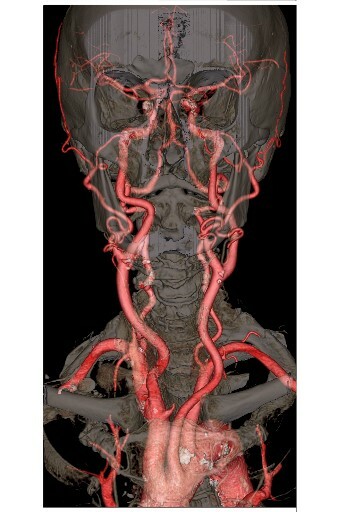

skull x-ray

CT angiography uses X-rays to view blood flow in blood vessels throughout the body, from arteries serving the brain to those bringing blood to the lungs, kidneys, arms, and legs. Beams of X-rays create cross-sectional images that are assembled by a computer into a three-dimensional picture of the area in question.

A CTA may be recommended for a variety of reasons. CTA helps visualize blood flow in the arteries that serve your kidneys, in patients with high blood pressure and those who are suspected of having kidney disorders. It also is used to identify life threatening aneurysms in heart and brain. CTA also can help detect narrowing and blockage in the arteries.